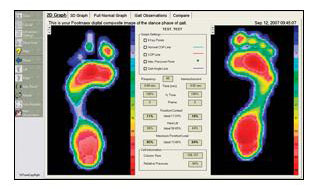

Click on the Button below for information on our new state of the art orthotic technology by Footmaxx.